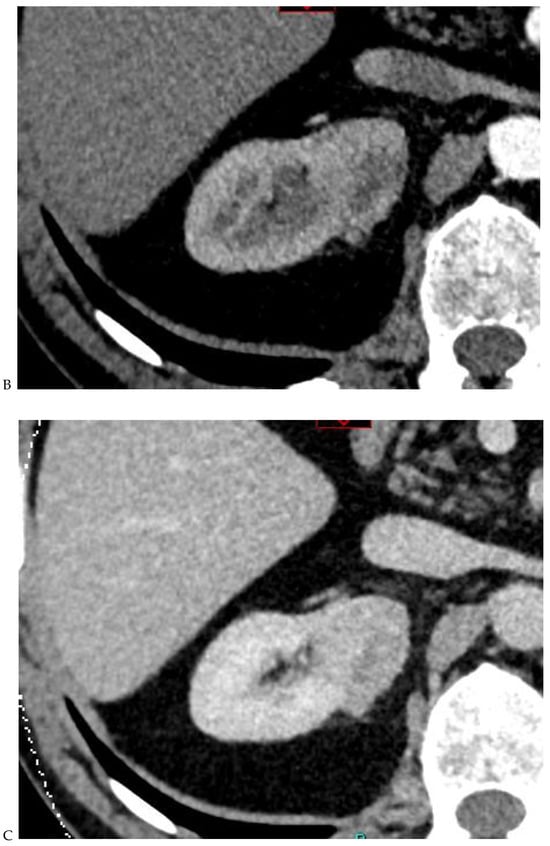

Figure 4.

Multiphasic CT enhancement of a papillary renal cell carcinoma in the middle part of the right kidney of a 63-year-old woman. (A) Mean unenhanced attenuation was 35 HU. (B) Mean corticomedullary phase attenuation was 45 HU. (C) Mean nephrographic phase attenuation was 59 HU. (D) Mean excretory phase attenuation was 65 HU.